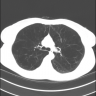

This article presents a detailed summary of the diagnosis, staging, and surgical management of early stage thymic malignancies.